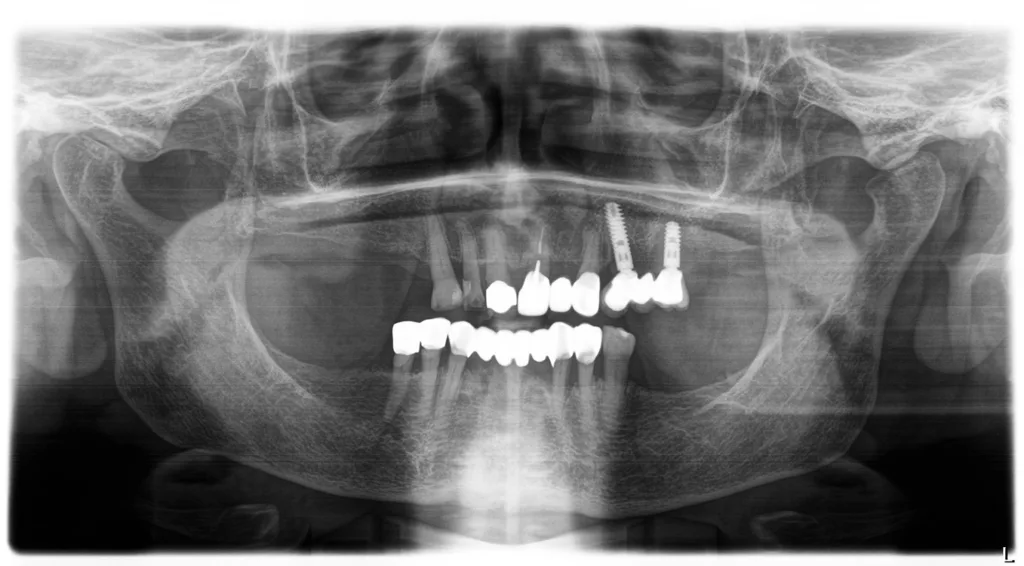

| Sekundo et al. 2020 | Periodontal and periimplant diseases in centenarians | 55/35/33 | > 60 Prozent der Teilnehmer mit eigenen Zähnenca. 4 Prozent der Teilnehmer mit Implantaten>70 Prozent der bezahnten Teilnehmer wiesen erhöhten parodontalen Behandlungs-bedarf auf |

Fast alle Befragten konnten den Wunsch nach einem Zahnarztbesuch äußern, aber ein Drittel der Teilnehmer/-innen wäre nicht mehr imstande gewesen, diesen zu organisieren [18]. Etwa 50% der Teilnehmenden hatten im vergangenen Jahr eine Zahnarztpraxis besucht und reinigten die Zähne oder Prothesen so wie vorgeschlagen zwei- bis dreimal pro Tag [18]. 20 Teilnehmer/-innen waren vollständig zahnlos [19,20]. Die Anzahl fehlender Zähne der Probanden/-innen wies eine große Varianz auf und betrug durchschnittlich 22 Zähne [20]. Von 35 bezahnten Teilnehmern/-innen [19] wiesen sieben eine weitgehend natürliche Dentition mit oder ohne festsitzende prothetische Versorgungen auf [20]. Bei sieben Patienten/-innen waren insgesamt 30 Implantate inseriert [19]. 48 Teilnehmer/-innen trugen eine herausnehmbare Teil- oder Totalprothese [20]. Etwa ein Drittel der herausnehmbaren Prothesen wurde als insuffizient (z.B. hinsichtlich Passung, Reparaturbedürftigkeit, Druckstellen oder Sauberkeit) eingestuft.

Für detaillierte parodontale und/oder periimplantäre Untersuchungen standen 33 Teilnehmer/-innen mit insgesamt 332 Zähnen (durchschnittlich 9,5 Zähne/Teilnehmer/-in) und 27 Implantaten zur Verfügung [19]. Die mittlere Anzahl von Zähnen mit moderat erhöhten Sondierungstiefen (ST ≥ 4 mm) betrug 3,9 und die mit deutlich erhöhten Sondierungstiefen (ST ≥ 6 mm) 0,7. Das bedeutete, 27,3% der Untersuchten (n = 9) wiesen keine ST ≥ 4 mm, 39,4% (n = 13) ST 4–5 mm und 33,3% (n = 11) ST ≥ 6 mm auf. Von allen 332 untersuchten Zähnen wiesen ca. 7% (n = 24) eine erhöhte Beweglichkeit auf [19]. Von den zur Untersuchung zur Verfügung stehenden Molaren (n = 59) wiesen lediglich drei Zähne einen Furkationsgrad 1 auf [19]. Drei Implantate (zwei Teilnehmende) konnten nicht weiter untersucht werden. Von den verbliebenen 27 Implantaten (fünf Patienten/-innen) wiesen 16 Implantate gesunde periimplantäre Verhältnisse auf, acht zeigten eine Mukositis und drei wurden mit Periimplantitis diagnostiziert. Der mittlere DMFT-Index betrug ca. 25 [18], und die Wurzelkariesprävalenz betrug 34,5%.

Walter/DoganDen Heidelberger Daten (HD-Z100) zufolgebesteht bei Hundertjährigen ein hoher parodontologischer, restaurativer und prothetischer Behandlungsbedarf [18–20]. In diesen Studien wurde auch die mundbezogene Lebensqualität untersucht. Demnach werteten ca. 60% der hier untersuchten Kohorte ihre orale Lebensqualität als nicht zufriedenstellend [20]. Die mundgesundheitsbezogene Lebensqualität wird dabei offenbar wesentlich durch die Anzahl fehlender Zähne beeinflusst. Im Umkehrschluss legt dies einen positiven Effekt des möglichst langen Zahnerhaltes nahe. Die kürzlich entsprechend der Leitlinien der parodontologischen Fachgesellschaft neu implementierte parodontale Behandlungssystematik dient auch diesem Ziel. Darüber hinaus ist die Lebensqualität durch festsitzenden Zahnersatz im Vergleich zu herausnehmbaren Prothesen weniger oder gar nicht eingeschränkt.

Viele der hier herausgearbeiteten Merkmale Hundertjähriger treffen tatsächlich auch auf die in den Abbildungen 6 bis 12 vorgestellte 99-jährige Dame zu. Eine weitere therapeutische Herausforderung stellt die Insuffizienz zahlreicher Prothesen dar [20]. Herausnehmbare prothetische Arbeiten erfordern regelmäßige Kontrollen und entsprechende Anpassungen. Die reduzierte Mobilität älterer und sehr alter Menschen schränkt die Möglichkeiten hierzu allerdings ein und stellt hohe Anforderungen an die aufsuchende zahnmedizinische Versorgung [30].